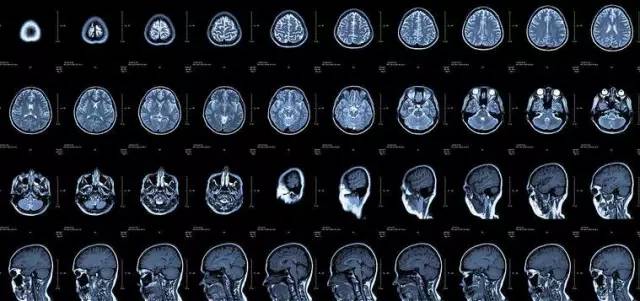

CT

像把面包切片看

CT的检查原理是X线会分层穿过人体,之后通过电脑计算后二次成像,就像把一片面包切成片来看。优点是可以分层看,经计算后可以显示出更多的组织信息。